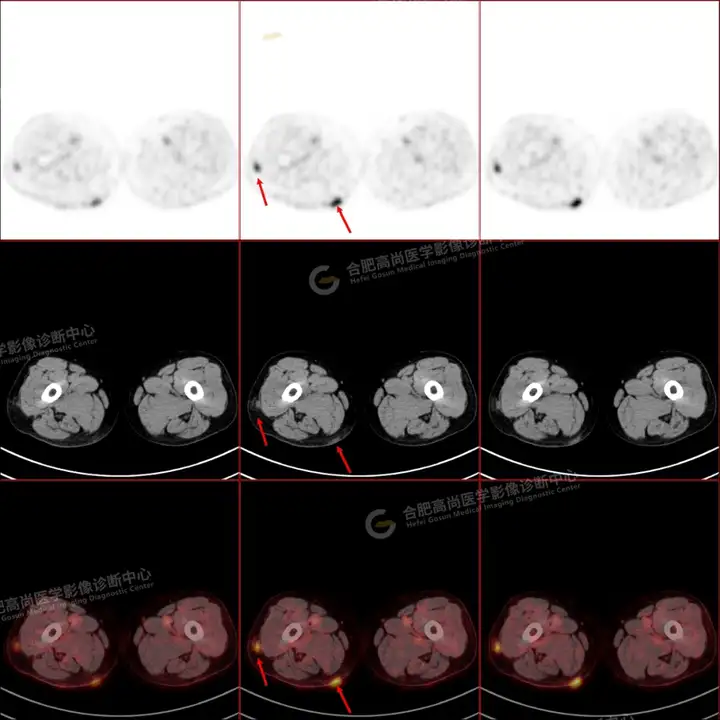

PETCT检查所示:图1、3-17全身多处(双上臂、胸背部、左侧乳腺、左侧腰部、腹壁、双侧臀部及双侧大腿)皮肤下结节及肿块样软组织密度灶,FDG代谢不同程度增高,双侧颈部、左侧锁骨区、纵隔内(1区)及双侧腋窝多发肿大淋巴结,FDG代谢明显增高,符合皮肤来源淋巴瘤。

图2右侧颈部包块切除术后,右侧锁骨区术区皮下片状密度增高灶,FDG代谢异常增高,考虑术后炎性反应。